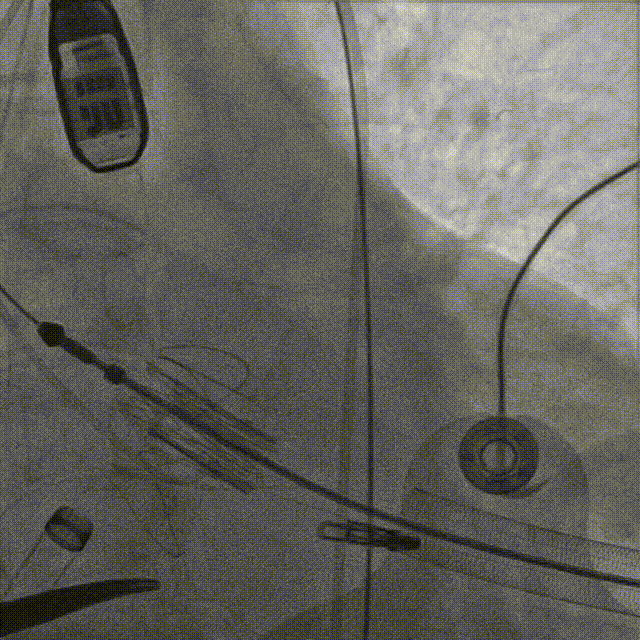

主动脉根部造影后,介入器跨瓣:

定位件进入窦部:

将瓣膜件降至合适水平面:

释放瓣膜后,复查根部造影,未见明显反流,瓣膜形态和位置满意,双侧冠脉显影良好:

复查超声显示主动脉瓣架深度合适、位置稳定,瓣叶启闭正常,未见明显瓣周反流: